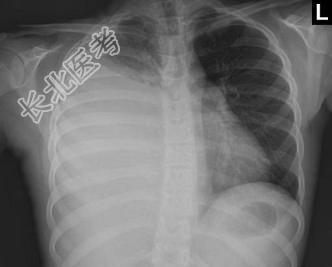

- 单项选择题下列图像最佳诊断是什么 ( )

A、脓胸

B、气胸

C、肺不张

D、肺癌

E、肺结核